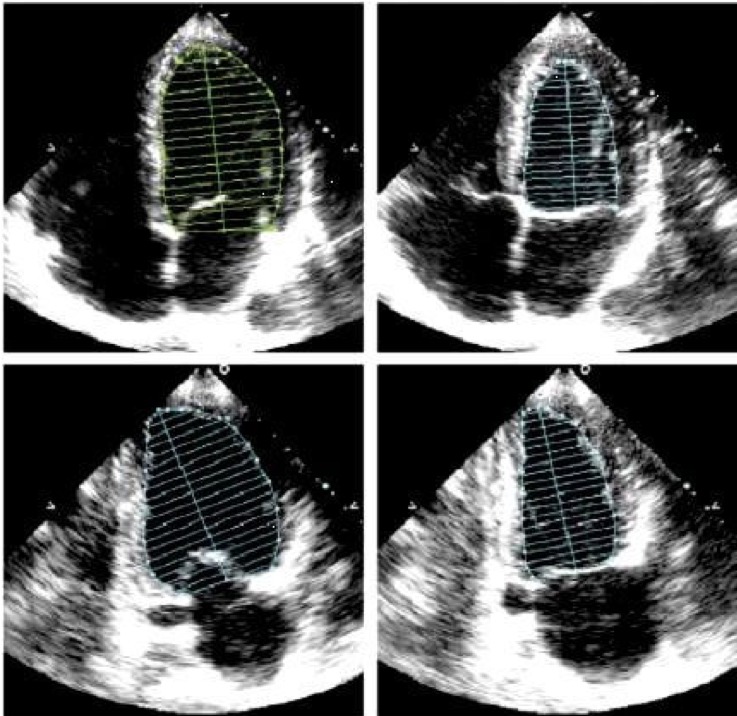

Симпсону и тейхольцу

Симпсону и тейхольцу 105 фотографий